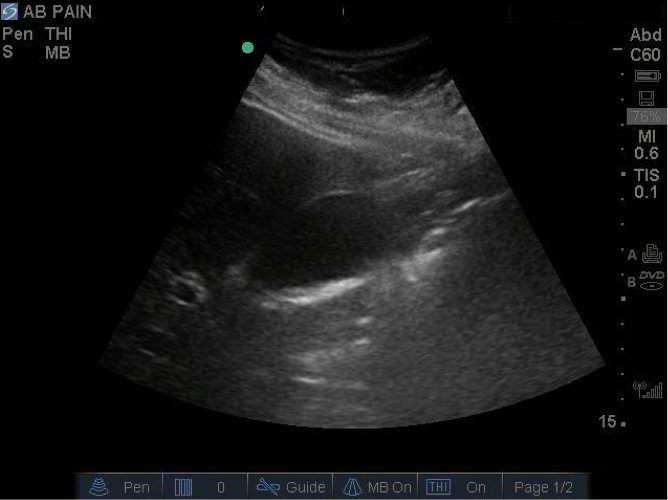

Gallbladder Posterior Acoustic Enhancement Image